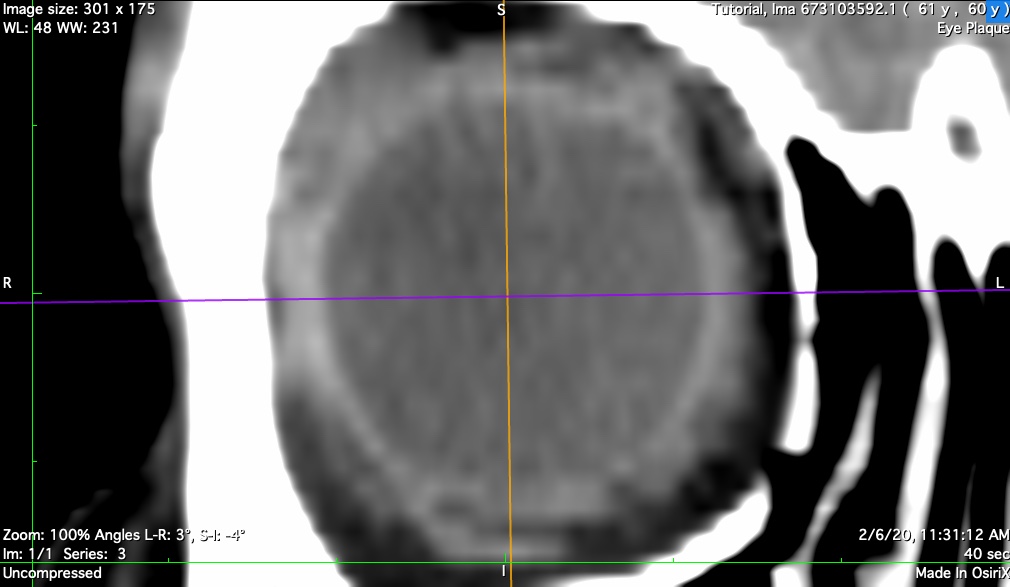

axial

Axial bisecting reconstruction. Used to determine optic disc center, nerve sheath diameter, and anterior oblateness of the eye. The sheath diameter determines how closely the plaque shell and seeds can approach the disc. This distance becomes important for extremely posterior and peripapillary tumors.

n-axial

Axial bisector illustrating the nerve-coronal plane (blue axis)